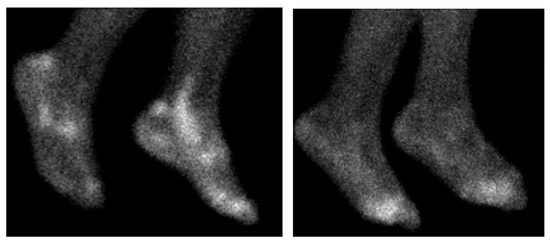

- Lee, S.J.; Hong, C.M.; Cho, I.; Ahn, B.-C.; Eun, J.S.; Kim, N.R.; Kang, J.W.; Kang, Y.M. Reappraisal of bone scintigraphy as a new tool for the evaluation of disease activity in patients with rheumatoid arthritis. Sci. Rep. 2021, 11, 21809. [Google Scholar] [CrossRef]

- Kim, J.Y.; Choi, Y.Y.; Kim, C.W.; Sung, Y.-K.; Yoo, D.-H. Bone Scintigraphy in the Diagnosis of Rheumatoid Arthritis: Is There Additional Value of Bone Scintigraphy with Blood Pool Phase over Conventional Bone Scintigraphy? J. Korean Med. Sci. 2016, 31, 502. [Google Scholar] [CrossRef]